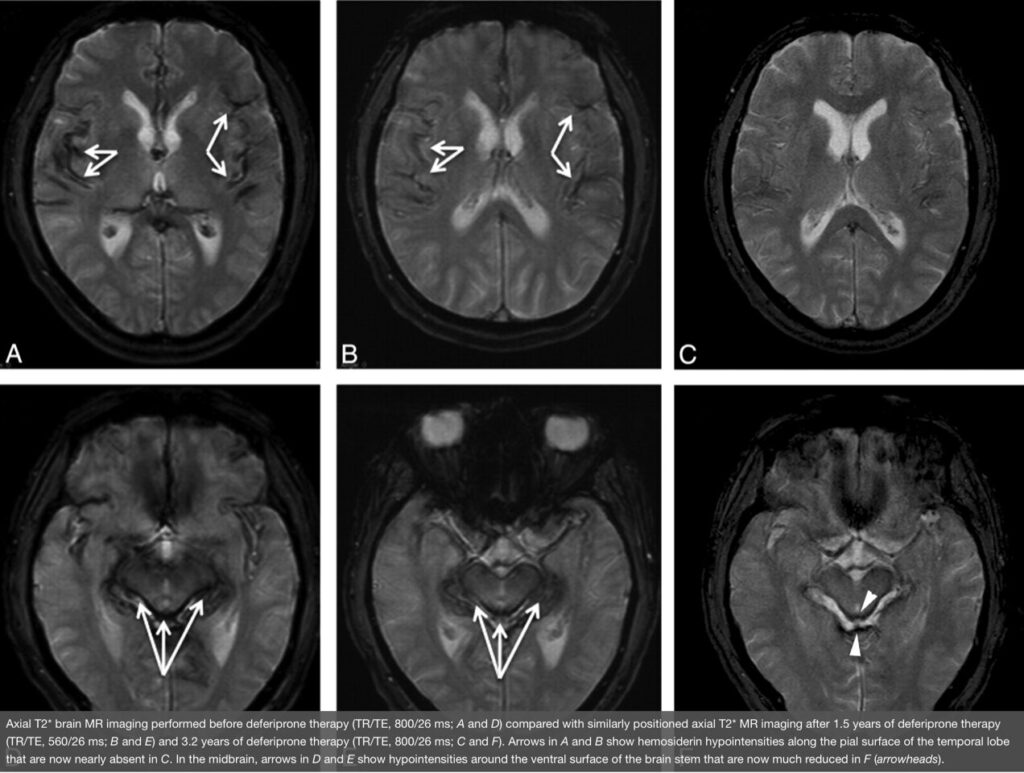

- 鉄キレート薬 デフェリプロン(deferiprone)は、血液脳関門を通過しうる脂溶性鉄キレート薬として研究されており、MRI上の鉄沈着低減の報告があります。 J-STAGE+2国立バイオテクノロジー情報センター+2